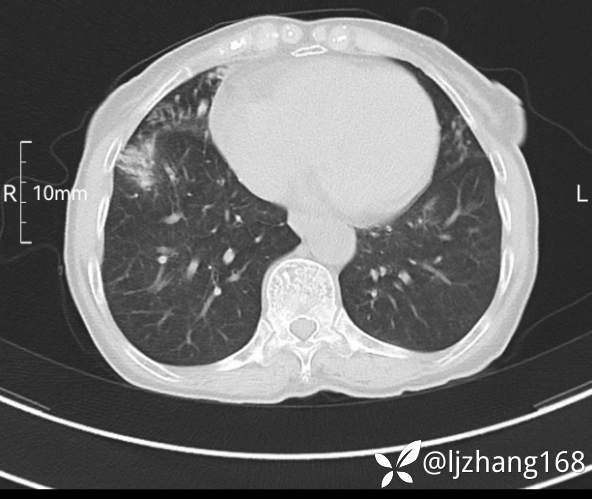

74岁女患,反复咳嗽2月,右肺空洞性病变,炎症OR肿瘤(有病理)

简要病史:2月前开始受凉后出现咳嗽,咳少许白色粘液痰,痰不易咳出,无痰中带血及咯血,无畏寒发热,外院胸部CT提示右下肺空洞病变,脓肿可能性大,常规抗感染治疗效果不佳。既往否认“糖尿病”等病史,有高血压基础病史,无吸烟史。

辅助检查:胸部CT右肺下叶前基底段结节并空洞

临床诊断:右肺空洞:脓肿?